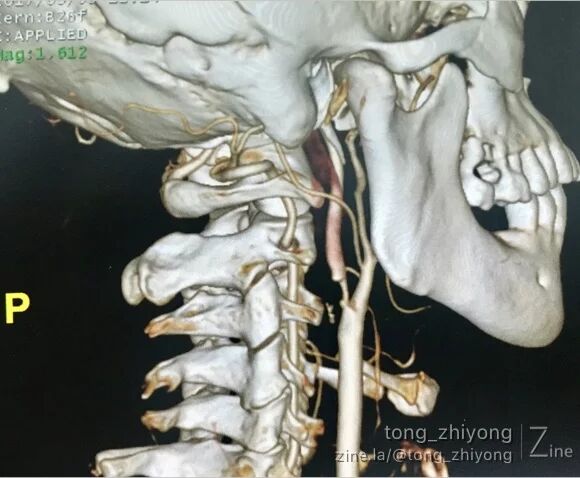

右侧颈动脉重度狭窄

CTA可见:右侧颈动脉重度狭窄,动脉粥样硬化斑块破裂,造影剂进入斑块。

术后一周CTA可见:颈动脉通畅,颈内动脉起始部管径适度增宽。